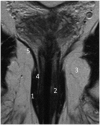

Although a rare disease, anal cancer is increasingly being diagnosed in patients with risk factors, mainly anal infection with the human papilloma virus. Magnetic resonance imaging (MRI) with external phased-array coils is recommended as the imaging modality of choice to grade anal cancers and to evaluate the response assessment after chemoradiotherapy, with a high contrast and good anatomic resolution of the anal canal. MRI provides a performant evaluation of size, extent and signal characteristics of the anal tumor before and after treatment, as well as lymph node involvement and extension to the adjacent organs. MRI is also particularly helpful in the assessment of complications after treatment, and in the diagnosis for relapse of the diseases.